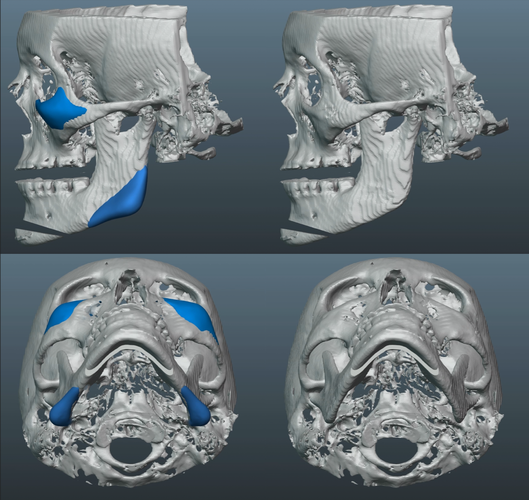

Just finished up this case and sent it to production.

-Patient also desired more volume around the infras and malars.

-About 8mm right and 10mm left widening on jaws.

-Both sides of jaw about 4.5mm height added.

-Concavity to jaw shape added/fixed.

-Inframalars are 4.5mm and 5.5mm from 3/4 view.

-Fixed general asymmetries.

-3.1mm saddle.

-Infra rim shape has a slight, but improved, curve to keep a natural look.

Old silicone wraparound:

Old silicone wraparound: